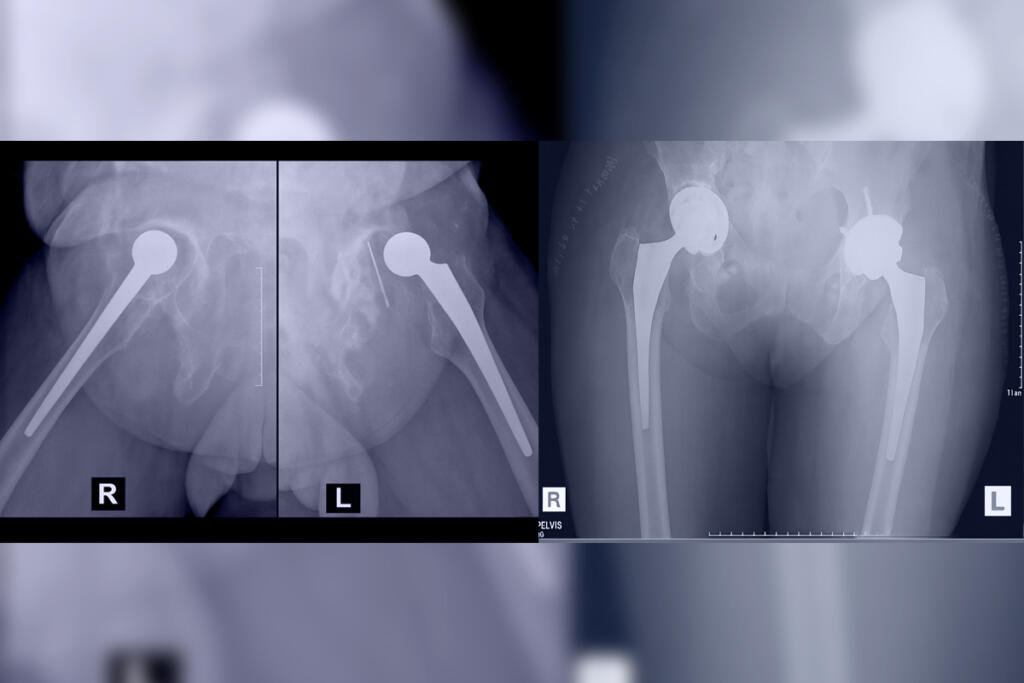

Revision Hip Replacement

Revision Hip Replacement is a surgical procedure that replaces a previously implanted hip prosthesis to correct complications or failures...